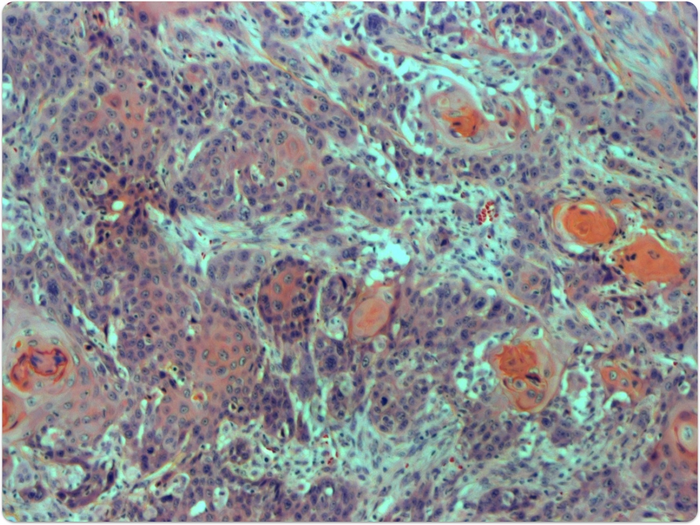

image: A cross section of a HNSSC tumor from a Fanconi anemia patient. view more

Credit: Laboratory of Genome Maintenance